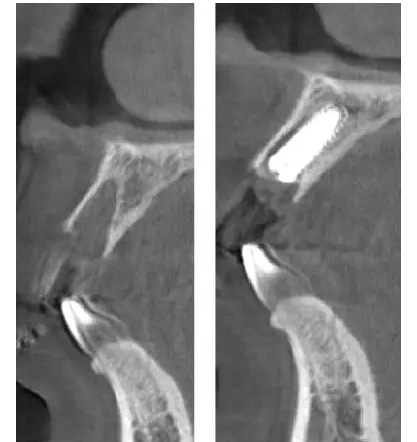

術(shù)前、術(shù)后CT

在口腔種植領(lǐng)域中,由于各種原因造成的種植牙局部牙槽突骨量不足或種植體周圍骨缺損的修復在種植外科的研究中已經(jīng)取得了重大突破。新一代的血漿提取物--濃縮生長因子(CGF,Concentrate Growth Factors)能夠明顯縮短術(shù)區(qū)成骨的時間,提高成骨質(zhì)量,促進成骨及組織的愈合;具體有:引導骨再生技術(shù)、聯(lián)合骨膜表面覆蓋加速軟組織愈合、用于上頜竇提升、拔牙后即刻種植、牙槽嵴位點保存、頜骨囊腫的治療、牙槽骨修整。